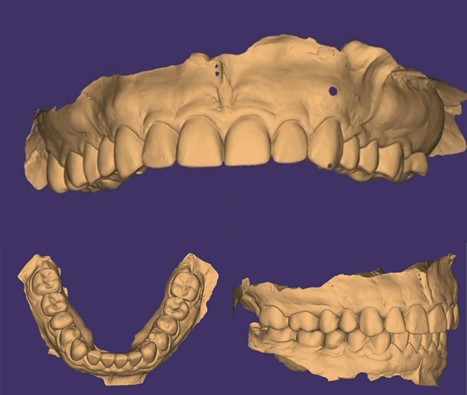

- STL-файлы в виде сканов верхней и нижней челюстей.

Сканы обточенных зубов для временных коронок

Цифровая модель зубов